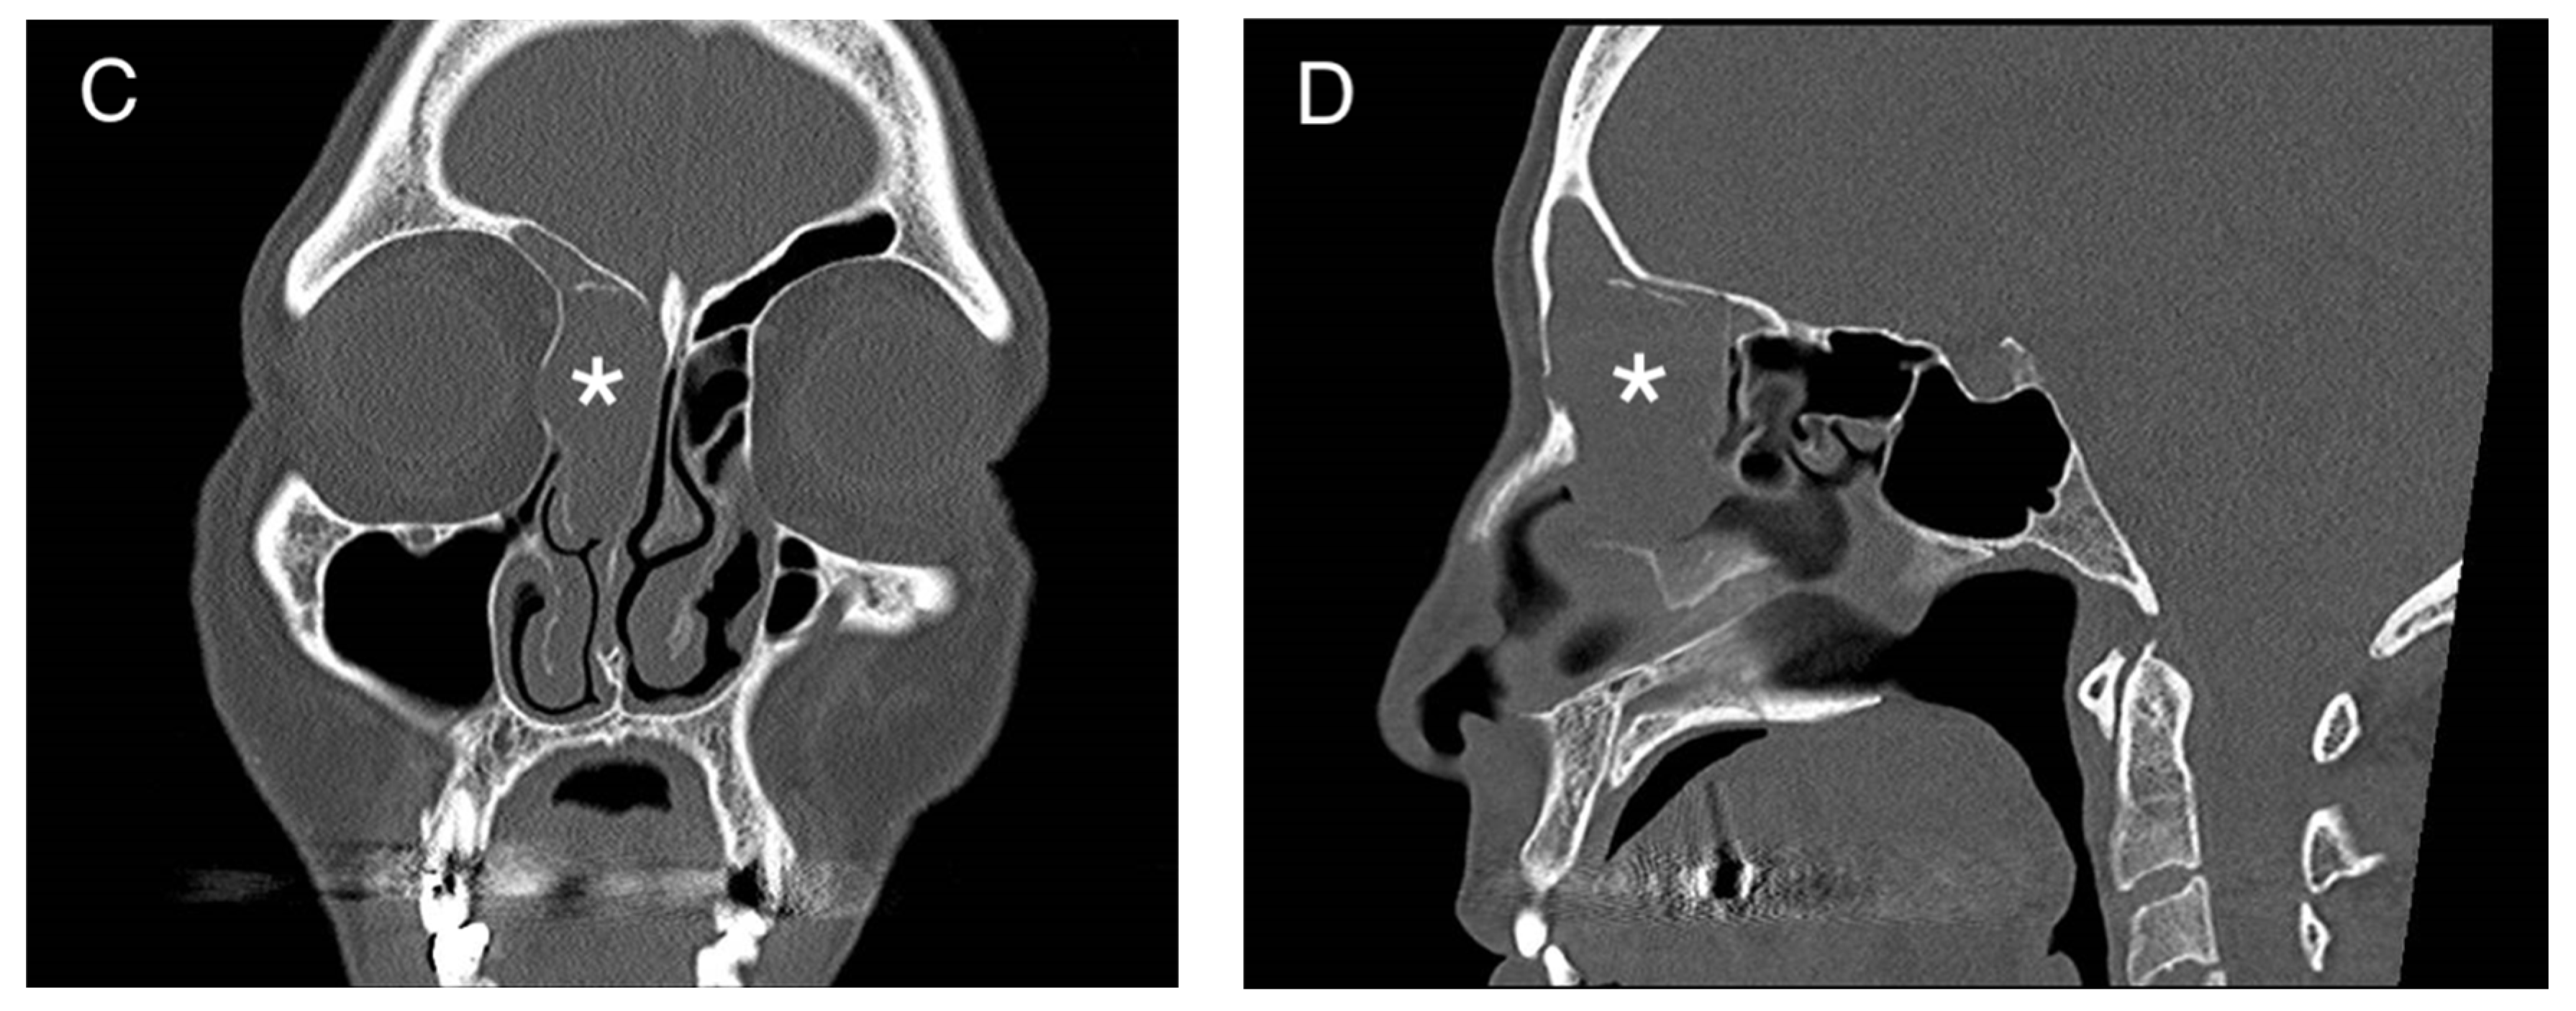

2. Presentation of Case